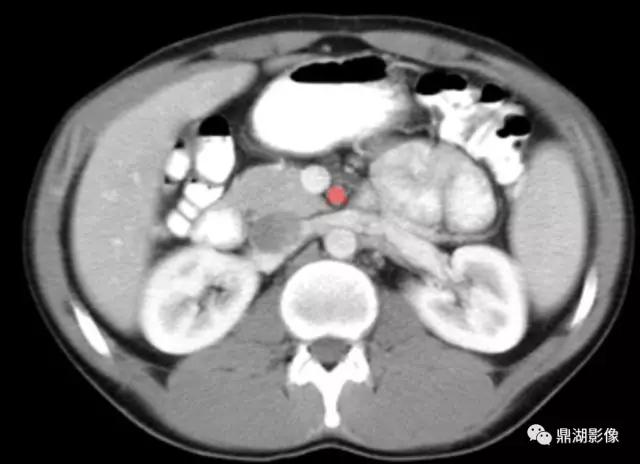

脾静脉(Splenic Vein)

肠系膜上静脉(Superior Mesenteric Vein)

肠系膜上动脉(Superior Mesenteric Artery)